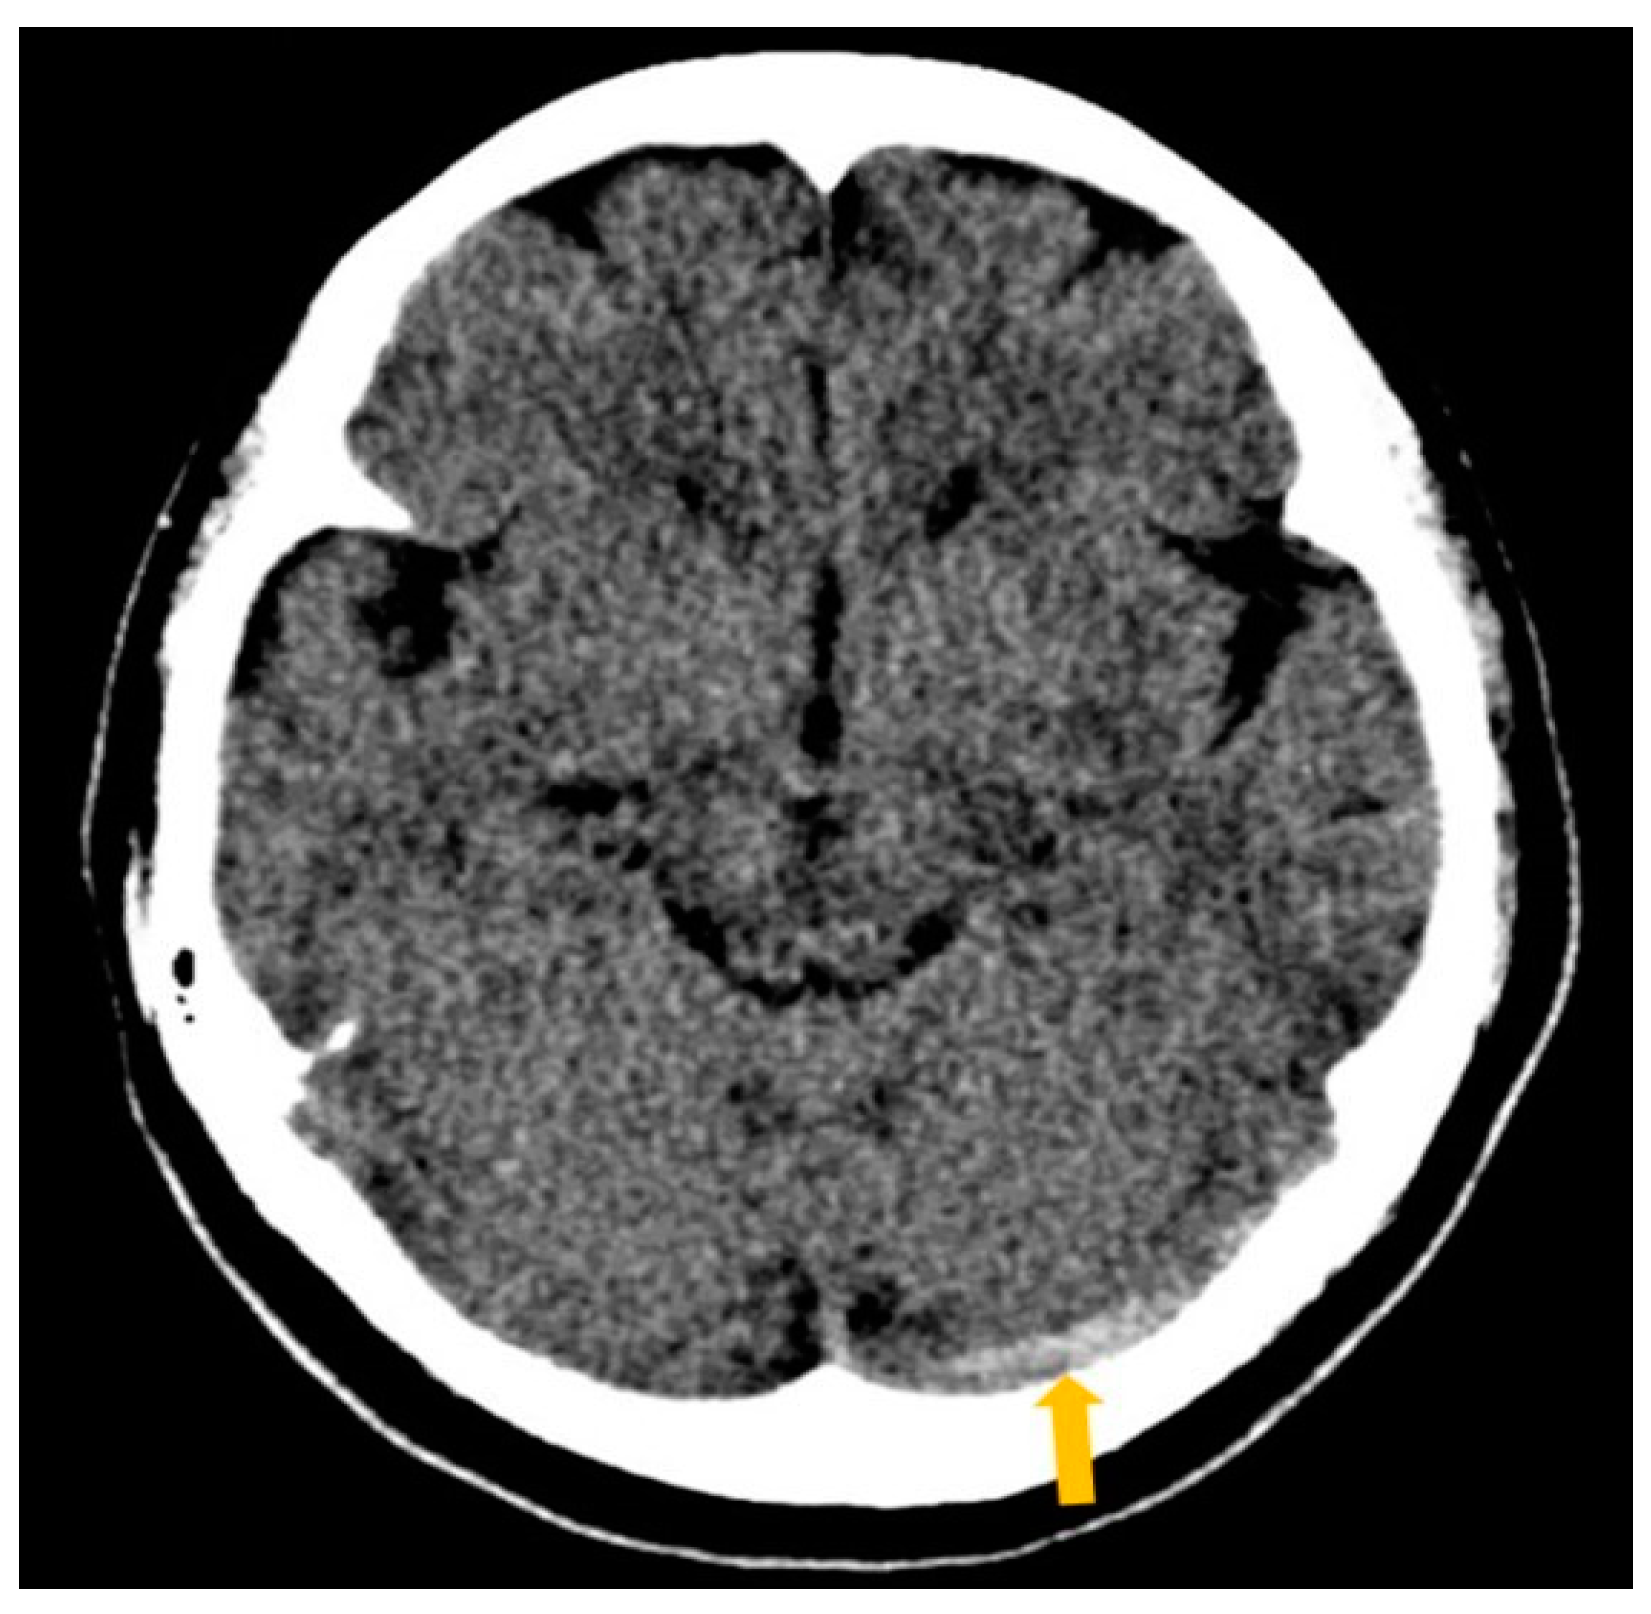

2. Case Report